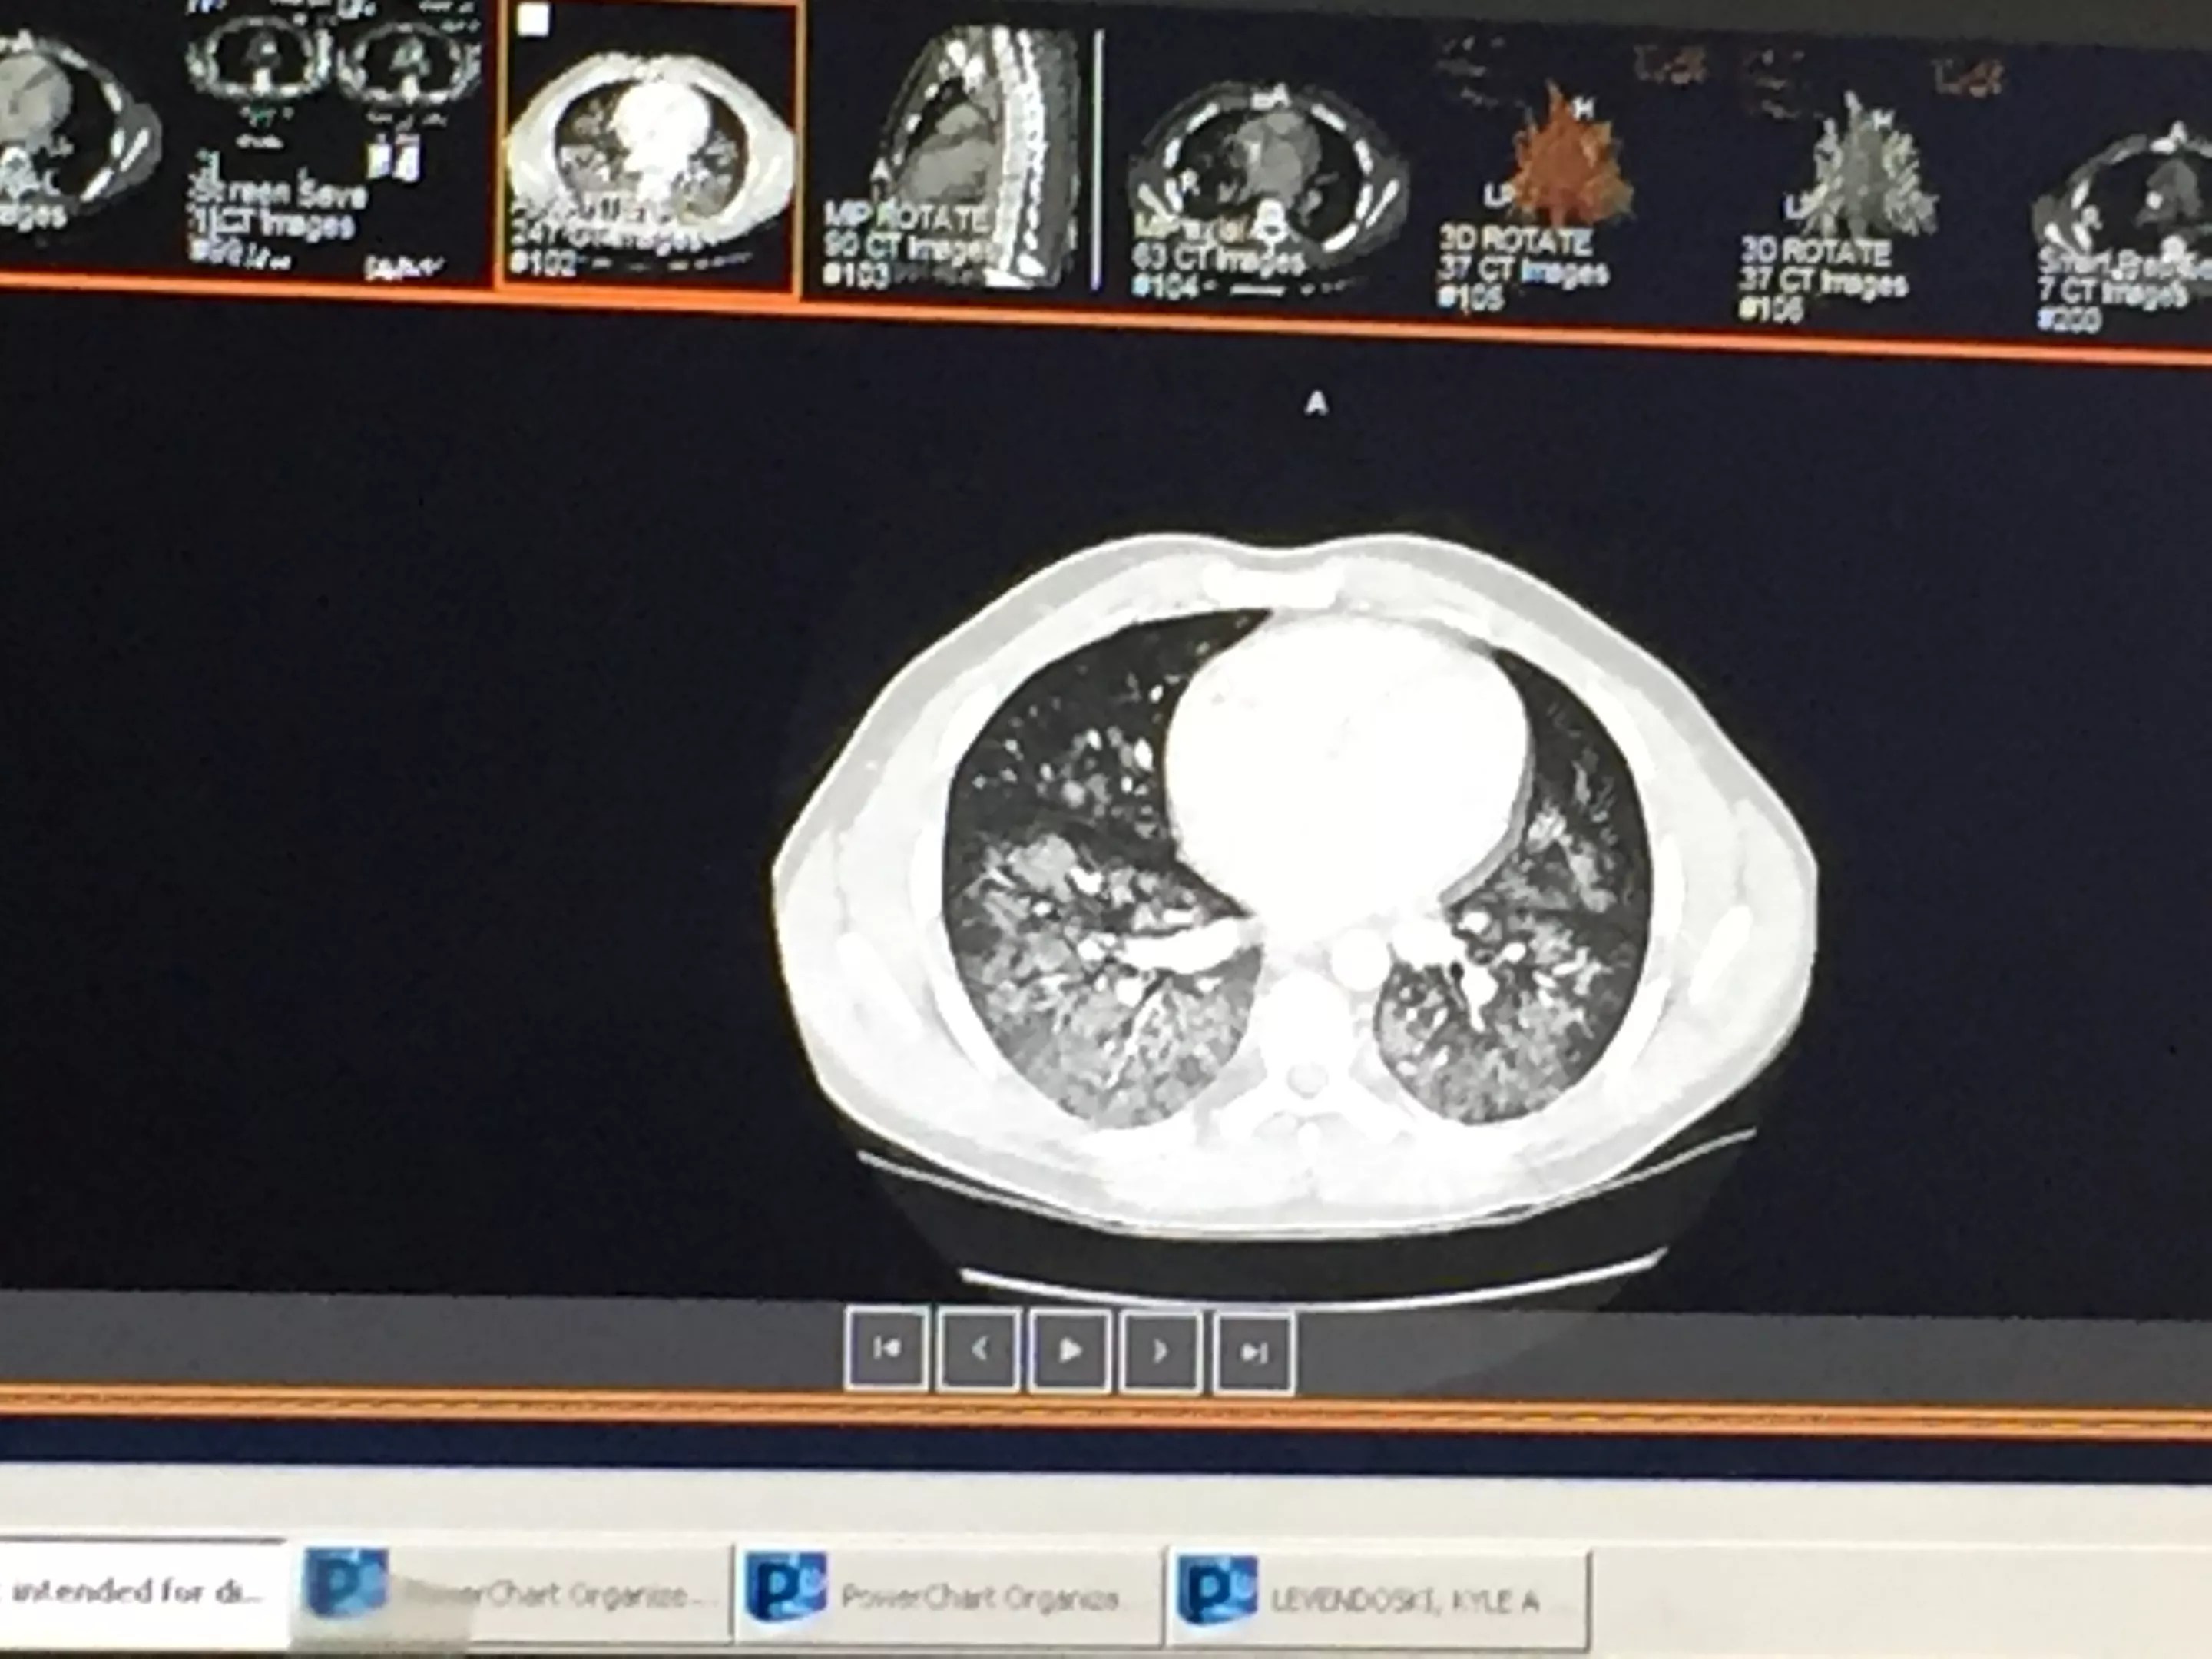

After his violent vomiting incident on September 4, he was taken to Abrazo Scottsdale Campus hospital and immediately put on oxygen therapy, which wasn’t stopped until he left on Saturday. After undergoing testing that included MRI and CT scans, he was diagnosed with a type of pneumonia caused by chemicals.

From his hospital bed, Levendoski watched news footage of others who had come down with similar pulmonary illnesses. He began comparing the images of those patients’ lungs with his own. “I looked on my phone to see how my lungs looked and how theirs looked. Mine looked worse!”